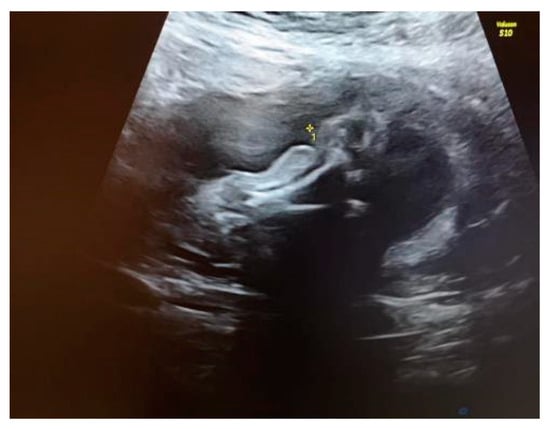

We explained to the parents that this anomaly was isolated. Because of the unilaterality of the defect, it was less likely that this was associated with underlying chromosomal abnormalities or genetic syndromes. The amniocentesis results showed a normal karyotype and normal array CGH. Our diagnosis was amniotic band syndrome. This is a rare finding when a fibrous amniotic band entangles parts of the fetus and constrict the blood supply to a specific part and causes the deformity of different parts of the fetus (see Figure 2).

Figure 2. Visualization of the constricted area of the right shin.